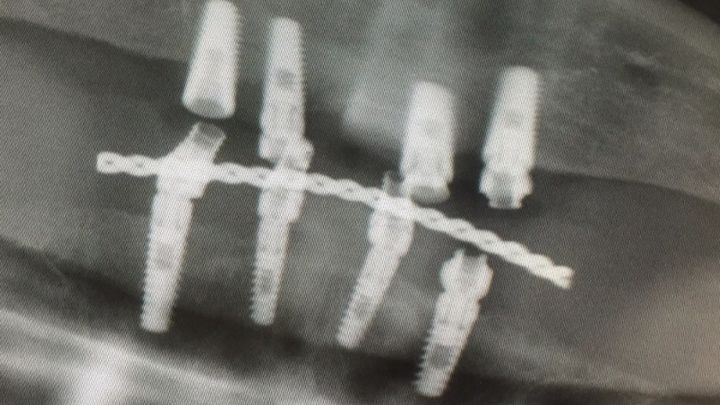

In 2014, we discovered an infection in the jawbones of my face that slowly started causing sepsis and damage to other areas of my body. We had to move quickly, and before long, I underwent surgery in November 2014 to have dental implants drilled into my jawbones after the damaged sections of bone had been removed.

Unfortunately, the original doctor placed the screws too close together. This issue has caused the bones between the screws to be weak and lacking in structure. The screws themselves are actually mobile and have failed completely and must be replaced. If they are not replaced, more bone will be lost and eventually, there will no longer be a treatment for this situation. There is also a risk of the damaged bone becoming infected once more, landing us back at square one.

To repair the damage, the new doctor will need to take out all four bottom screws and will need to replace them with four new ones in the bottom jaw. The top jaw will also need two screws to be added in the back to help give it more stability. Besides that, the top jaw is mostly okay for the time being; should it become an issue, we can come back and treat that at a much later date. This condition is not one that can simply be solved with a normal pair of dentures. The structure and shape of my mouth is not compatible with any other treatment, and malnutrition has become quite the issue as of late.

Unfortunately, the original doctor placed the screws too close together. This issue has caused the bones between the screws to be weak and lacking in structure. The screws themselves are actually mobile and have failed completely and must be replaced. If they are not replaced, more bone will be lost and eventually, there will no longer be a treatment for this situation. There is also a risk of the damaged bone becoming infected once more, landing us back at square one.

To repair the damage, the new doctor will need to take out all four bottom screws and will need to replace them with four new ones in the bottom jaw. The top jaw will also need two screws to be added in the back to help give it more stability. Besides that, the top jaw is mostly okay for the time being; should it become an issue, we can come back and treat that at a much later date. This condition is not one that can simply be solved with a normal pair of dentures. The structure and shape of my mouth is not compatible with any other treatment, and malnutrition has become quite the issue as of late.